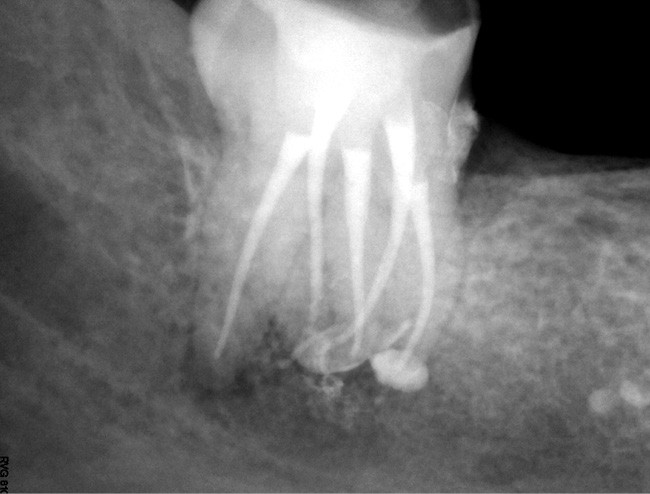

Comme mentionné précédemment, l’insuffisance instrumentale dans la préparation canalaire n’est plus à démontrer.

Si les isthmes sont particulièrement mis en évidence au niveau des molaires mandibulaires, cela devient médicalement important au niveau des molaires maxillaires.

La diffusion bactérienne et de leurs toxines, au niveau des molaires maxillaires est à l’origine d’un grand nombre de sinusites maxillaires chroniques, d’origine dentaire. Celles-ci sont principalement causées par l’absence de traitement du deuxième canal MV, qui existe dans 90 % des cas, et il est à noter que ces deux canaux – MV1 et MV2 – sont également reliés par un isthme.

Le nettoyage des isthmes intercanalaires reste un réel problème, et semble responsable de nombreux échecs [43]. Par ailleurs, il est nécessaire d’utiliser des instruments qui évitent de propulser les débris, tant apicalement que latéralement, en obturant les entrées isthmiques avec des débris compactés.

L’utilisation d’instruments en nickel titane, tels que le XP Shaper (FKG), le Vortex blue (Dentsply) ou le Profile (Dentsply), optimise la remontée des débris et s’inscrit dans cette nouvelle philosophie. En conséquence, la combinaison XP Shaper, XP Finisher et l’irrigation avec l’Er:YAG semblent optimiser nos traitements [44,45].

Le passage du laser est répété plusieurs fois, en début, au milieu et en fin de préparation. Un protocole peut alors être proposé : 40 mJ ; 20 Hz (fig. 7). L’utilisation de biocéramiques Bioroot (Septodont) ou Total Fill R (FKG) permet de sceller le système ainsi nettoyé, en assurant une action biologique de longue durée [46] (fig. 8a à c).